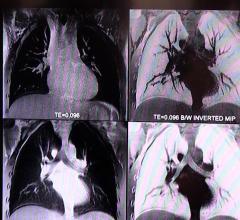

March 21, 2019 — Using data from computed tomography (CT) images, researchers may be able to predict which lung cancer ...